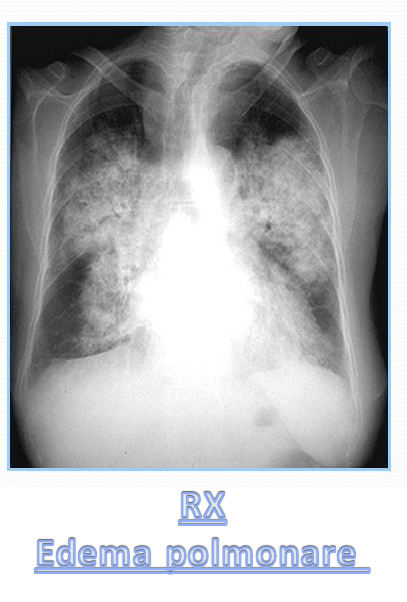

L’edema polmonare è una condizione clinica di emergenza che richiede un intervento immediato e si caratterizza per un eccesso di liquidi intra-alveolari che alterano gli scambi gassosi e il circolo.

Cause non cardiogene di edema polmonareLe complicanze possono presentarsi con disfunzione ventricolare sinistra, edema ad arti inferiori e gonfiore addominale, reflusso epato-giugulare per congestione severa del piccolo circolo, turgore giugulare, fino all’exitus del paziente. La sintomatologia è tipica di un quadro di insufficienza respiratoria (il reperto auscultatorio evidenzia rantoli) con dispnea, tosse, tachipnea, ipostenia e alterazioni significative al tracciato elettrocardiografico. La diagnosi è generalmente data dal binomio visita medica-radiografica torace. La terapia mira a decongestionare i polmoni dai fluidi e a garantire i corretti scambi gassosi, favorendo farmacologicamente il precarico e postcarico cardiaco per abbassare l’eventuale quadro di ipertensione arteriosa creatosi. Non è escluso che in casi gravi sia necessario somministrare ossigeno ad altri flussi (e/o posizionamento di casco CPAP) o ricorrere a una ventilazione assistita.